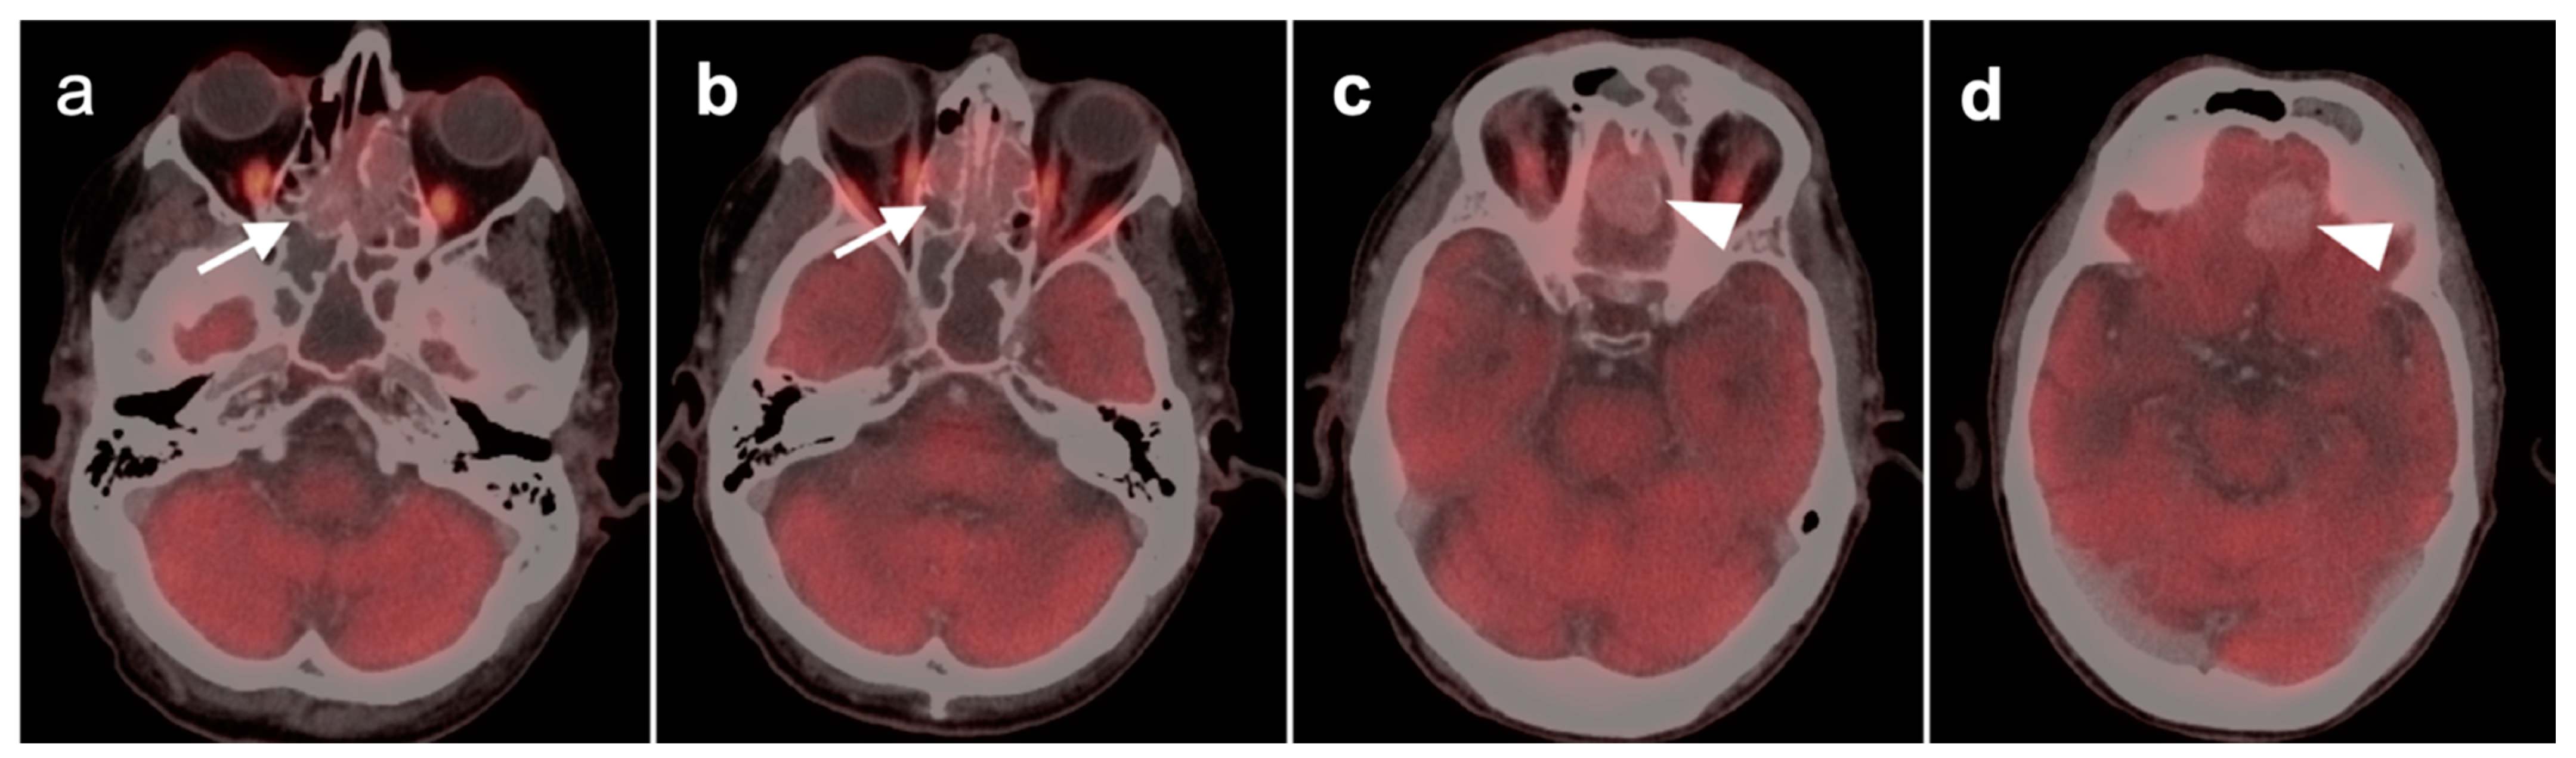

2.5. Major and Minor Salivary Gland, Lacrimal Gland Tumors

- Pleomorphic adenoma and carcinoma ex pleomorphic adenoma

- Warthin tumor